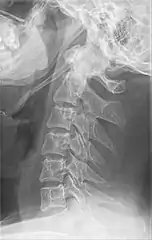

Radiograph, lateral view showing joint-like formation in ossified stylohyoid ligament

Imaging is important and is diagnostic. Visualizing the styloid process on a CT scan with 3D reconstruction is the suggested imaging technique.[12] The enlarged styloid may be visible on an orthopantogram or a lateral soft tissue X ray of the neck.